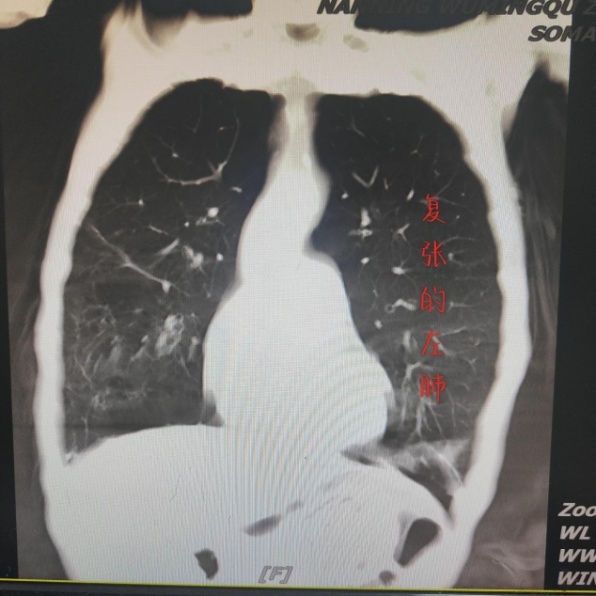

“今天吸氧,感觉没那么喘了”。邓大爷虽不了解吸氧与吸氧之间有何区别,但自觉气促症状好转。事实证明,他的感觉是对的,联合经鼻高流量湿化氧疗后,邓大爷胸腔闭式引流瓶中逐渐无水柱波动及气泡冒出,气胸症状明显改善。继续治疗4天后,复查胸部CT提示气胸已完全吸收,邓大爷顺利出院了。

CT复查提示左肺已完全复张